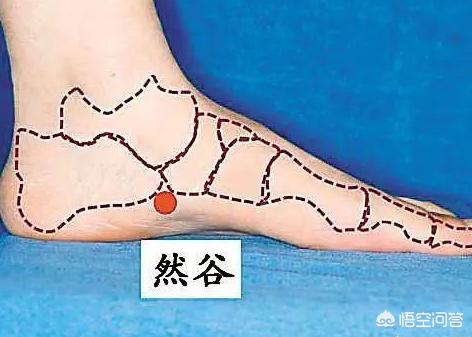

3、多くの場合、糖分を下げるポイントを押す

足の内側のくるぶしの骨を手で触ると、斜め前方2cmに高い骨があり、この高い骨の下端が乱宮のツボである。

ラングーのツボは、より深いところにエッセンスが隠れている場所にあるため、適度な力で押して、痛みや腫れを感じたら離し、また押して離すということを繰り返すことが大切である。

そのため、15~20回繰り返し行い、足を押してからもう片方の足を変え、一定期間を守ることで、ドライマウスや頻尿、尿意切迫感などの症状を効果的に緩和・治療することができる。